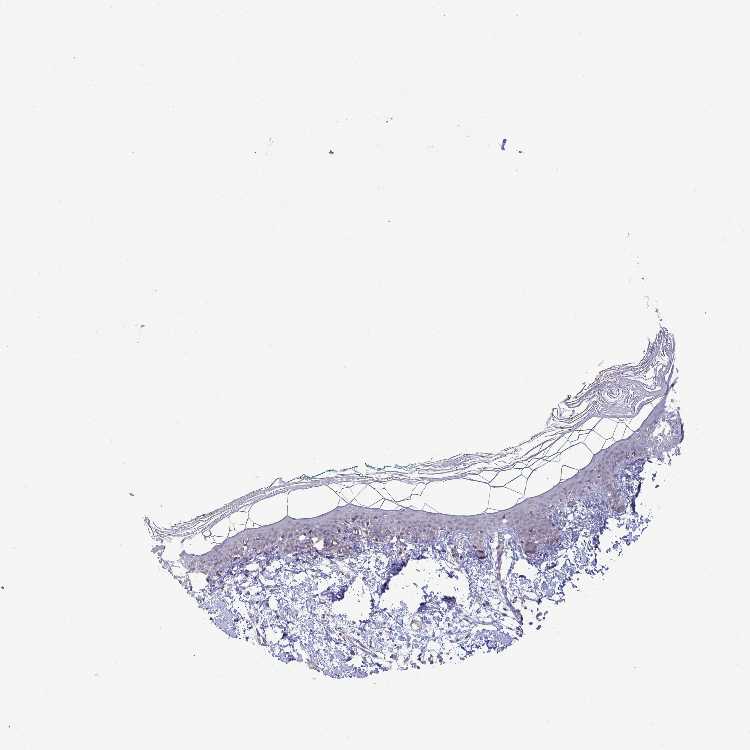

SKIN 2 - Antibody stainingi

Antibody staining in the annotated cell types in the current human tissue is reported as not detected, low, medium, or high, based on conventional immunohistochemistry profiling in selected tissues. This score is based on the combination of the staining intensity and fraction of stained cells.

Each image is clickable and will lead to virtual microscopy that enables deeper exploration of all samples and also displays staining intensity scores, fraction scores and subcellular localization as well as patient and tissue information for each sample.

Antibody HPA052730Antibody HPA056957

Epidermal cells MediumMedium